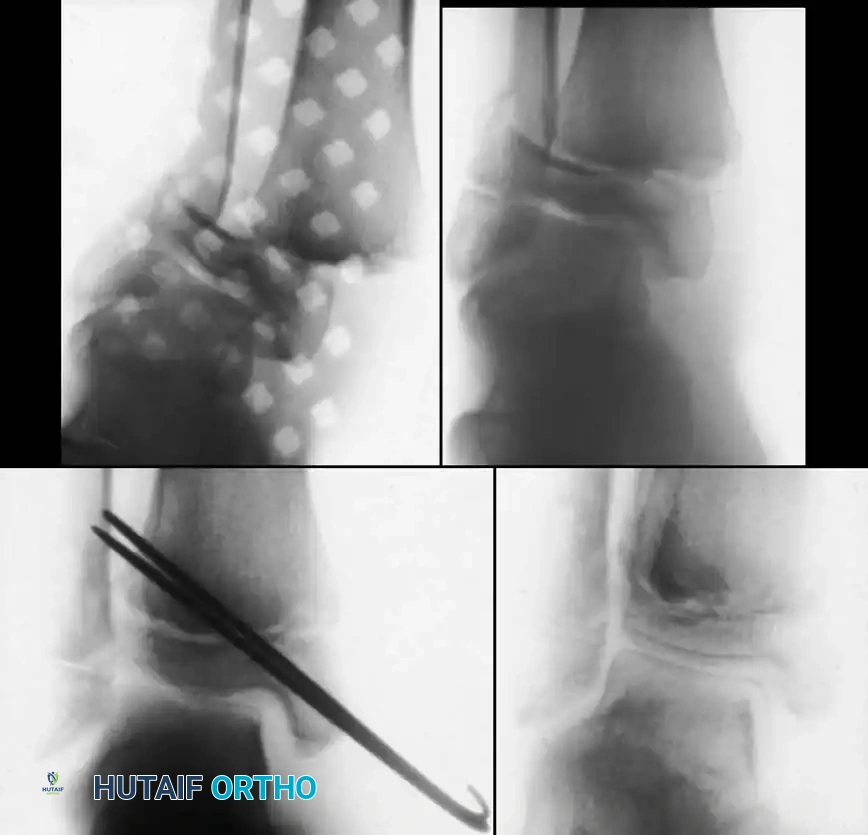

Intraoperative exposure demonstrating the parapatellar approach.

Elevation of the soft tissues to visualize the fracture hematoma.

Removal of interposed periosteum from the fracture site.

Direct visualization of the articular surface to ensure anatomic reduction.

Fluoroscopic confirmation of anatomic reduction prior to definitive fixation.

Placement of transverse fixation pins.

Final construct utilizing cancellous screws for rigid fixation.